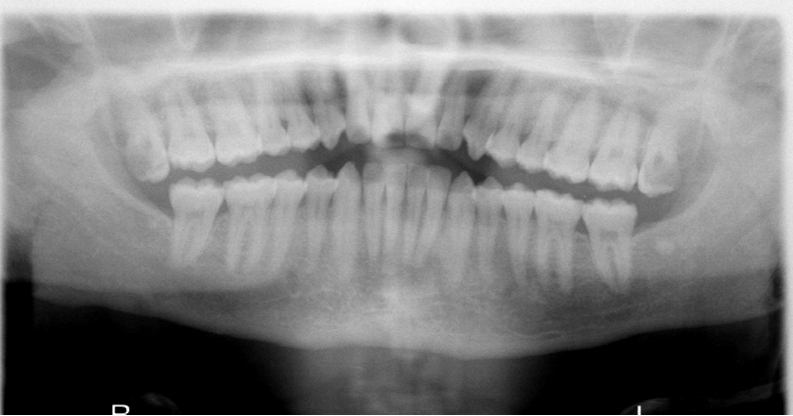

What is wrong with this image?

too far forward

double real image of cervical spine (superimposed on ramus)